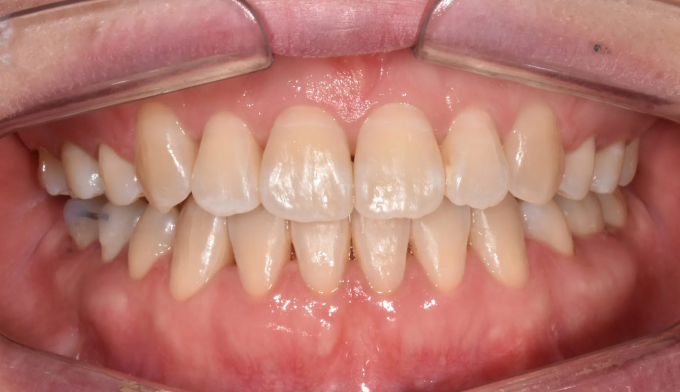

돌출입과 개방교합이 동시에 있는 경우에는 발치교정을 통해 앞니를 넣어주면 개방교합이 쉽게 개선됩니다. 이때 주의할점은 미소시 치아의 노출정도입니다. 또한 개방교합의 경우에는 재발 경향이 높기 때문에 주기적인 경과관찰이 필요하며 최종위치에 안정적으로 치아가 위치해있다고 판단이 들었을 때 교정치료를 종료하여야 합니다.

총 교정기간은 25개월입니다.